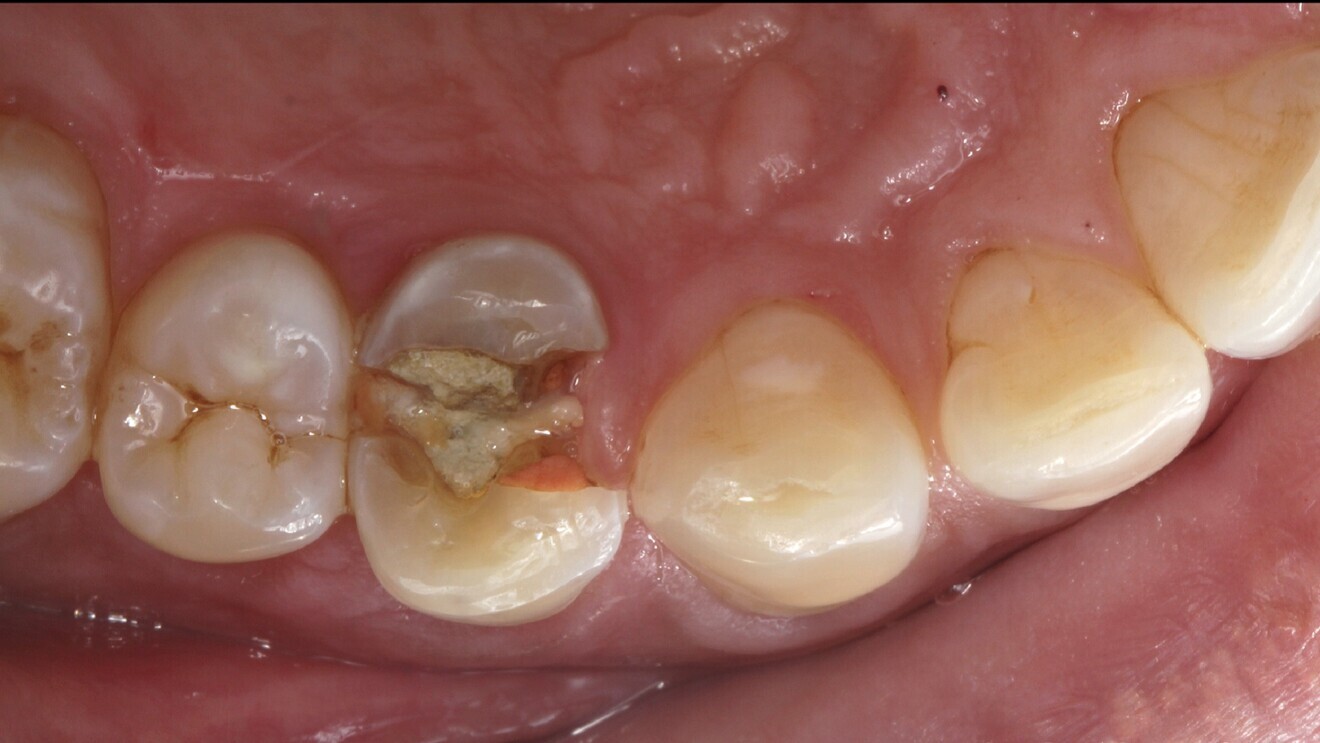

Fig. 6: Fractured tooth #14.

A 42-year-old male patient required extraction of his maxillary right first premolar (tooth #14; Fig. 6). The patient’s high smile line and need for immediate rehabilitation posed challenges. Atraumatic extraction preserved the tissue and bone profile (Fig. 7).